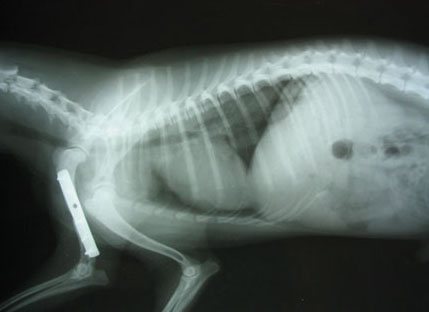

Контрольная рентгенограмма кошки после операции, в месте перелома установлена металлическая пластина.